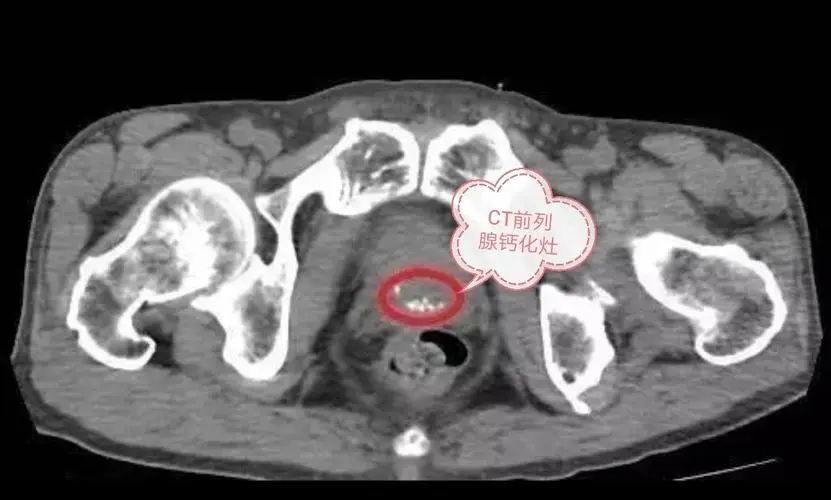

前列腺钙化

这可能是每一个男人都遇到的问题。前列腺钙化的形成,可能源于之前得过前列腺炎,康复后遗留下来的疤痕。如果没有排尿困难只需要定期复查就可以,不用过于担心,不是啥大事。